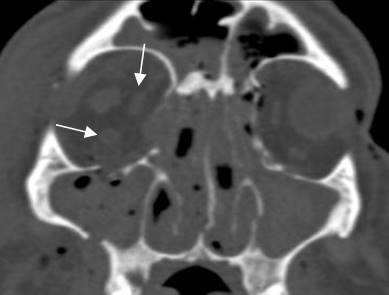

Fig 218 B. Fractura de órbita.

TAC axial. Fractura en el borde medial de la órbita con edema del músculo recto interno. Está desplazado medialmente y se debe sospechar su atrapamiento. (Flecha delgada). Adicionalmente hay cambios inflamatorios en el espacio intraconal e irregularidad del nervio óptico. (Flecha gruesa).